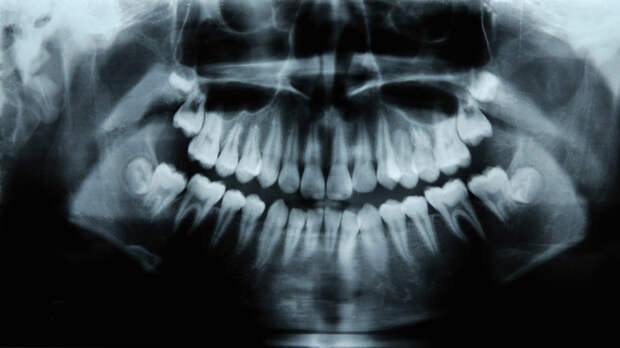

Важно не чистить язык до крови, а показаться врачу», — заявила эксперт в беседе с газетой «Известия».По словам специалиста, следует проходить профосмотр у стоматолога каждые шесть месяцев.